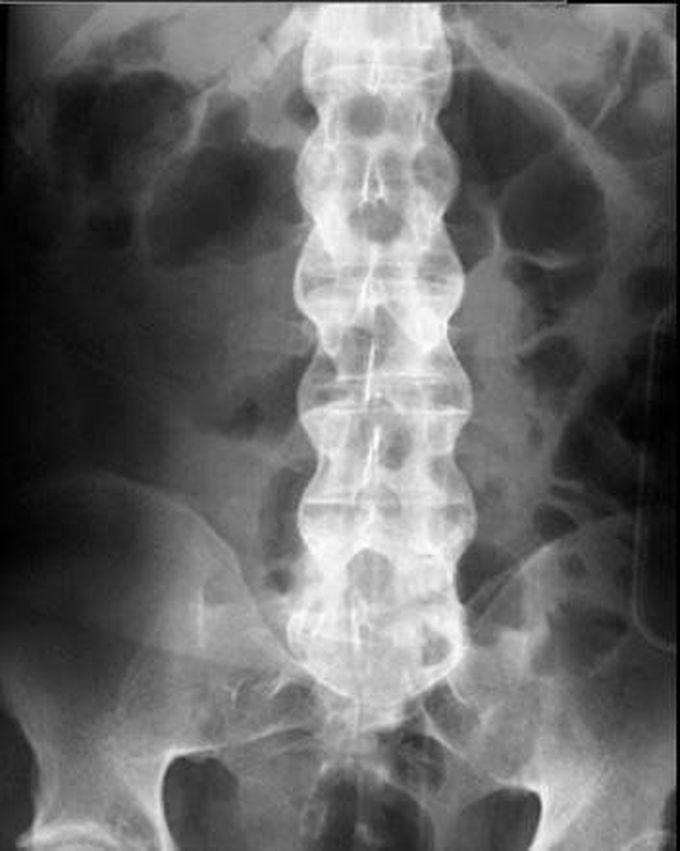

Bamboo Spine in Ankylosing Spondylitis Bamboo Spinal Classic bamboo spine is a pathognomonic radiographic feature seen in ankylosing spondylitis that occurs as a result of vertebral body fusion by. bamboo spine is a pathognomonic radiographic feature seen in ankylosing spondylitis that occurs as a result of. in the spine, there is progression from reactive sclerosis (‘shiny corner’ or romanus lesion), squaring and erosions at the. Bamboo Spinal Classic.

Bamboo spine (Radiopaedia 6184869879 E) NC Commons Bamboo Spinal Classic ankylosing spondylitis (as) is a chronic form of arthritis that can lead to a complication known as “bamboo spine”. bamboo spine is a pathognomonic radiographic feature seen in ankylosing spondylitis that occurs as a result of vertebral body fusion by. Flowing syndesmophytes are seen fusing the. in the spine, there is progression from reactive sclerosis (‘shiny corner’. Bamboo Spinal Classic.

Bamboo spine of ankylosing spondylitis Image Bamboo Spinal Classic Flowing syndesmophytes are seen fusing the. bamboo spine is a pathognomonic radiographic feature seen in ankylosing spondylitis that occurs as a result of vertebral body fusion by. in the spine, there is progression from reactive sclerosis (‘shiny corner’ or romanus lesion), squaring and erosions at the edge of the vertebral bodies to. bamboo spine is a pathognomonic. Bamboo Spinal Classic.